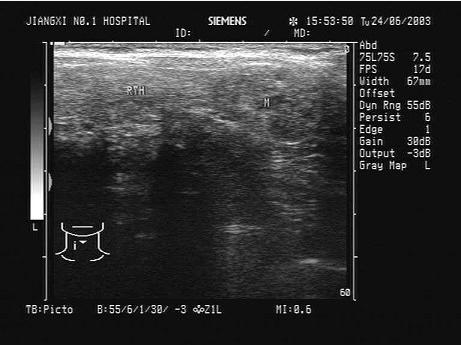

临床资料:女,48岁,常规体检。临床物理检查:双侧颈部形态饱满,甲状腺左叶有结节感,质韧。超声综合描述:双侧甲状腺增大,内可见不均质回声区,右叶中部不均质回声大小3.5cm×2.6cm,左叶不均质回声大小3.3cm×1.9cm,内回声明显不均,由低一中等回声,CDFI:不均质回声区内血流信号异常丰富,呈近似火海征,其余部分血流信号未见异常。见下图及彩图74。

超声提示()。

A.慢性淋巴细胞性甲状腺炎(桥本氏病)

B.甲状腺腺瘤

C.甲状腺癌

D.亚急性甲状腺炎